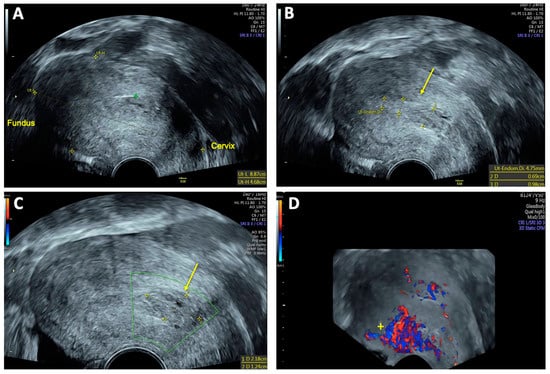

Post-interventional TVS performed 48 h after embolization demonstrated a marked reduction in the size of the AVM and the absence of the characteristic Doppler sonographic systolic/diastolic velocity differentiation, indicating successful vascular occlusion (Figure 5). Peridural catheter for analgesia was removed two days post-procedure, and the patient was discharged in stable condition on the same day.

Figure 5. Transvaginal sonography (TVS) 48 h after uterine arteriovenous malformation (AVM) embolization: (A) 2D TVS showing an enlarged retroflected uterus measuring 89 × 55 mm post-intervention; (B) 2D TVS with color Doppler demonstrating a hypoechoic lesion of 20 × 32 mm with minimal residual perfusion (arrow); (C) 2D TVS with color Doppler showing residual venous blood flow in the uterine cavity (*) and intense blood flow localized in the posterior uterine wall (+); (D) 3D TVS with color Doppler confirming persistent intense blood flow in the posterior uterine wall (+), with no significant perfusion of the AVM.